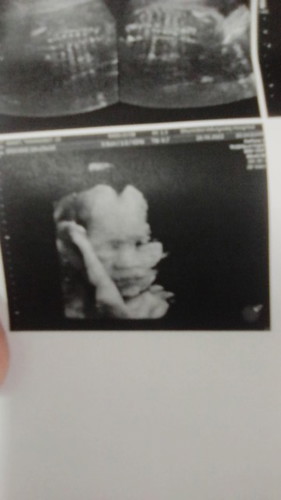

ช่วยตั้งชื่อลูกสาวหน่อยจ้า แม่ชื่อ ปาย พ่อชื่อ ต้า แม่ๆช่วยตั้ง#ท้องแรกคะ #ขอบคุณล่วงหน้านะคะ จ้า